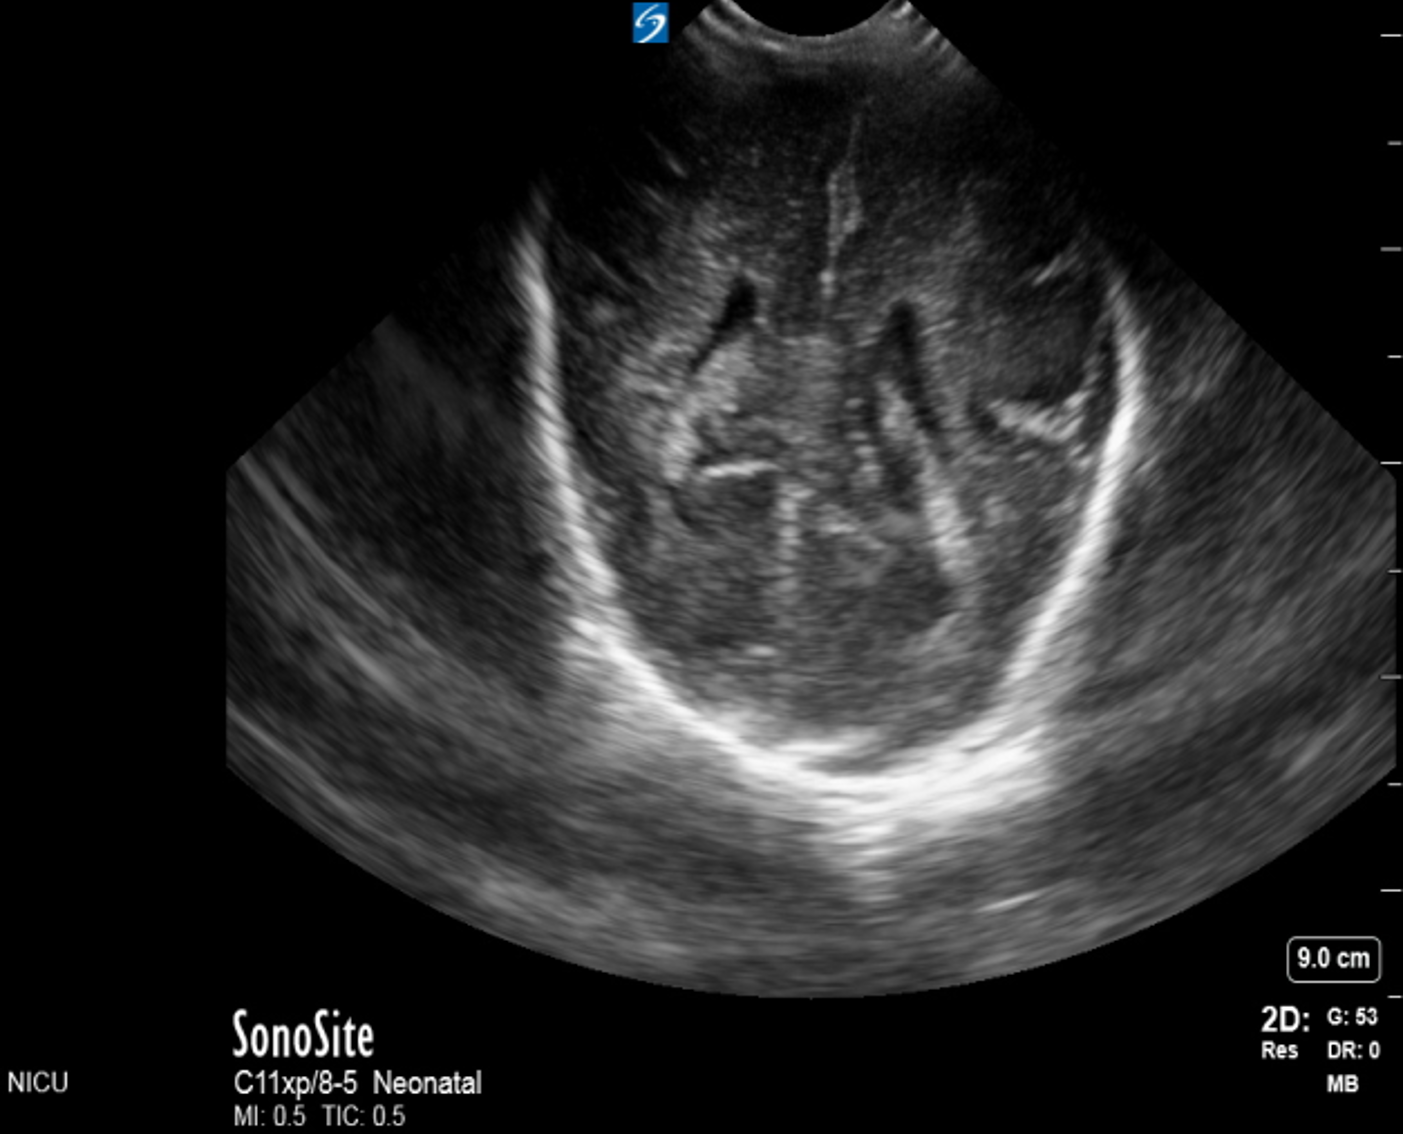

Neonatology Grade 2 IVH Coronal Image